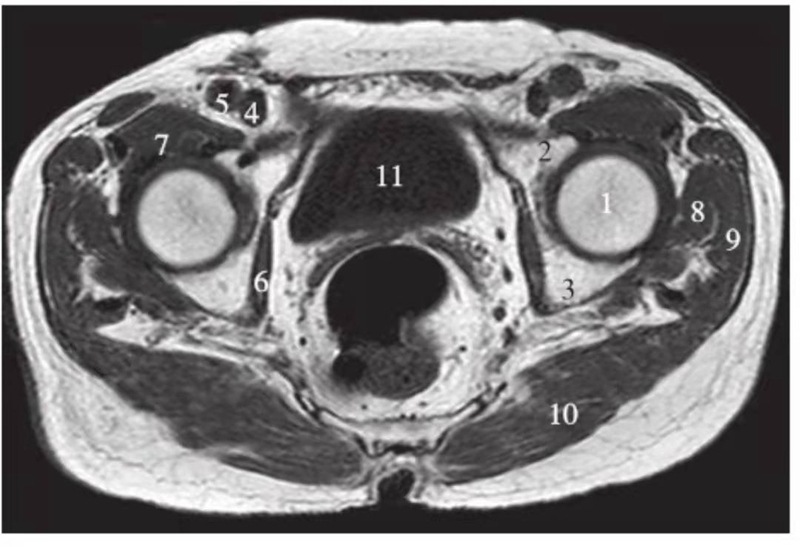

正常髋关节经股骨头中心层面T1WI像

1.股骨头;2.耻骨;3.坐骨;4.股静脉;5.股动脉;6.闭孔内肌;7.髂腰肌;8.臀小肌;9.臀中肌;10.臀大肌;11.膀胱

正常髋关节经股骨颈层面T1WI像

1.股骨头;2.股骨颈;3.转子间部;4.髋臼后唇;5.耻骨联合;6.髂腰肌;7.闭孔内肌;8.臀大肌